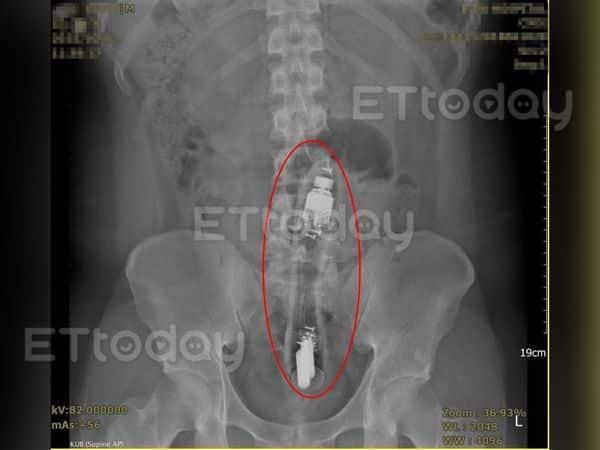

คุณหมอเฉินตรวจร่างกายพบว่ามีวัตถุแข็งติดอยู่ในทวารหนักของชายหนุ่ม จึงส่งไปเอ็กซ์เรย์ ยืนยันว่ามีวัตถุทรงแท่งยาว 15-20 เซนติเมตรติดอยู่ และแท่งนั้นได้เข้าไปลึกถึงลำไส้ใหญ่ส่วนคด

ดังนั้นเมื่อชายหนุ่มยินยอม ทีมแพทย์จึงตัดสินใจผ่าเอาสิ่งแปลกปลอมออกให้เขาในห้องฉุกเฉินทันที ชายหนุ่มมีความอดทนสูงมาก สุดท้ายทีมแพทย์จึงใช้เครื่องมือคล้ายคีมคีบเด็กทารก ค่อยๆ ดึงแท่งนั้นออกมา

คุณหมอเฉินเล่าว่า ดึงอยู่นานก็พบว่าเป็นแท่งนวดขนาดยาว เมื่อดึงออกมาหมดแล้ว แท่งนวดยังคงสั่นเล็กน้อย ทำให้ทีมแพทย์ถึงกับตะลึง บอกว่าแบตเตอรี่ทนทานมาก สั่นมาทั้งคืนยังไม่หมดไฟ แถมชายหนุ่มยังทำตัวได้นิ่งเฉยอีกด้วย